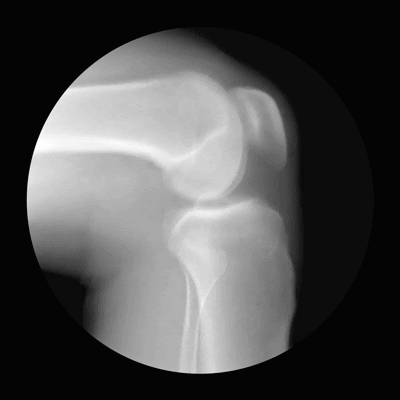

Also, in honour of the amazing science and diagnostic tool that is x-rays, here is a wonderful series of gifs by Cameron Drake and Dr Noah Weiss that show the joints of the human body in motion:

The knee cap

Human beings have a few different types of joints, including hinge joints (just like a hinge on a door, like in the knee), ball-and-socket (like in the shoulder, which allows wide rotation) and pivot joints (like the one at the top of your spine that allows you to rotate your head in a "no" motion). You don't really think about how they work until you start to have problems (or you are an anatomy student), but when you have a closer look, you can appreciate what an amazing machine the body is!